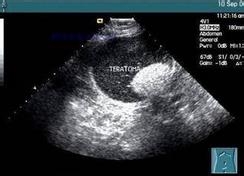

3、b超或是彩超。那就是最佳的检查啦,而且一目了然!可以更加直观的知道你的身体各部位的症状!